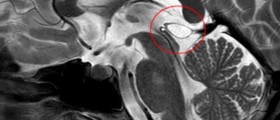

What Is A Pineal Cyst?

Medical Answer